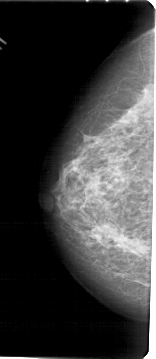

A_1705_1.LEFT_CC

LEFT_CC LINES 5371 PIXELS_PER_LINE 2326 BITS_PER_PIXEL 12 RESOLUTION 43.5 NON_OVERLAY